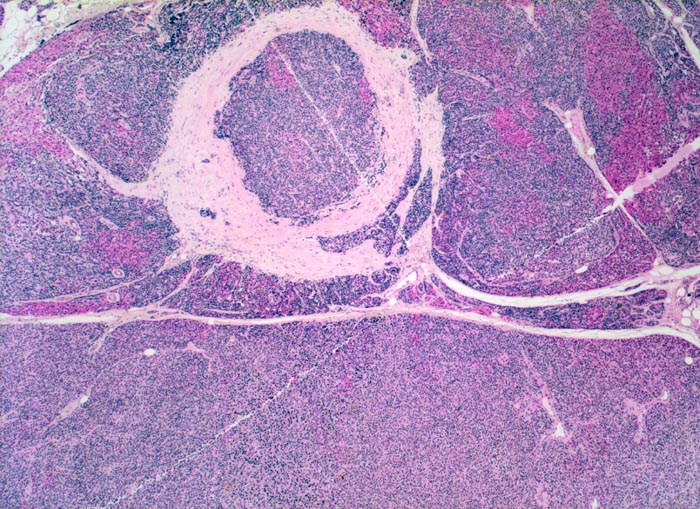

Morphologisch besteht bei sHPT eine Hauptzellhyperplasie. Makroskopisch findet sich eine meist ungleich ausgebildete Vergrösserung aller Nebenschilddrüsen. Die Grösse der Drüsen entspricht der Schwere und der Dauer des Stimulus. Die im früheren Stadium gefundene diffuse Hyperplasie mit Ersatz des Stromas und der Fettzellen durch chronisch stimulierte Hauptzellen (> 558) (> 559) geht im späteren Stadium in eine noduläre Hyperplasie („Pseudoadenome“) über (> 2358). Die regulierte Anpassung der Nebenschilddrüsen kann in eine Autonomie übergehen (tHPT) (> 3704). Morphologisch besteht in diesem Fall eine unregelmässige noduläre Hyperplasie. Gelegentlich entwickelt sich beim tHPT ein dominanter Knoten, der morphologisch nicht von einem Adenom bei pHPT unterscheidbar ist.

• Knotige vergrösserte Nebenschilddrüse. Abgrenzung der einzelnen Knoten durch breite Fibrosebänder.